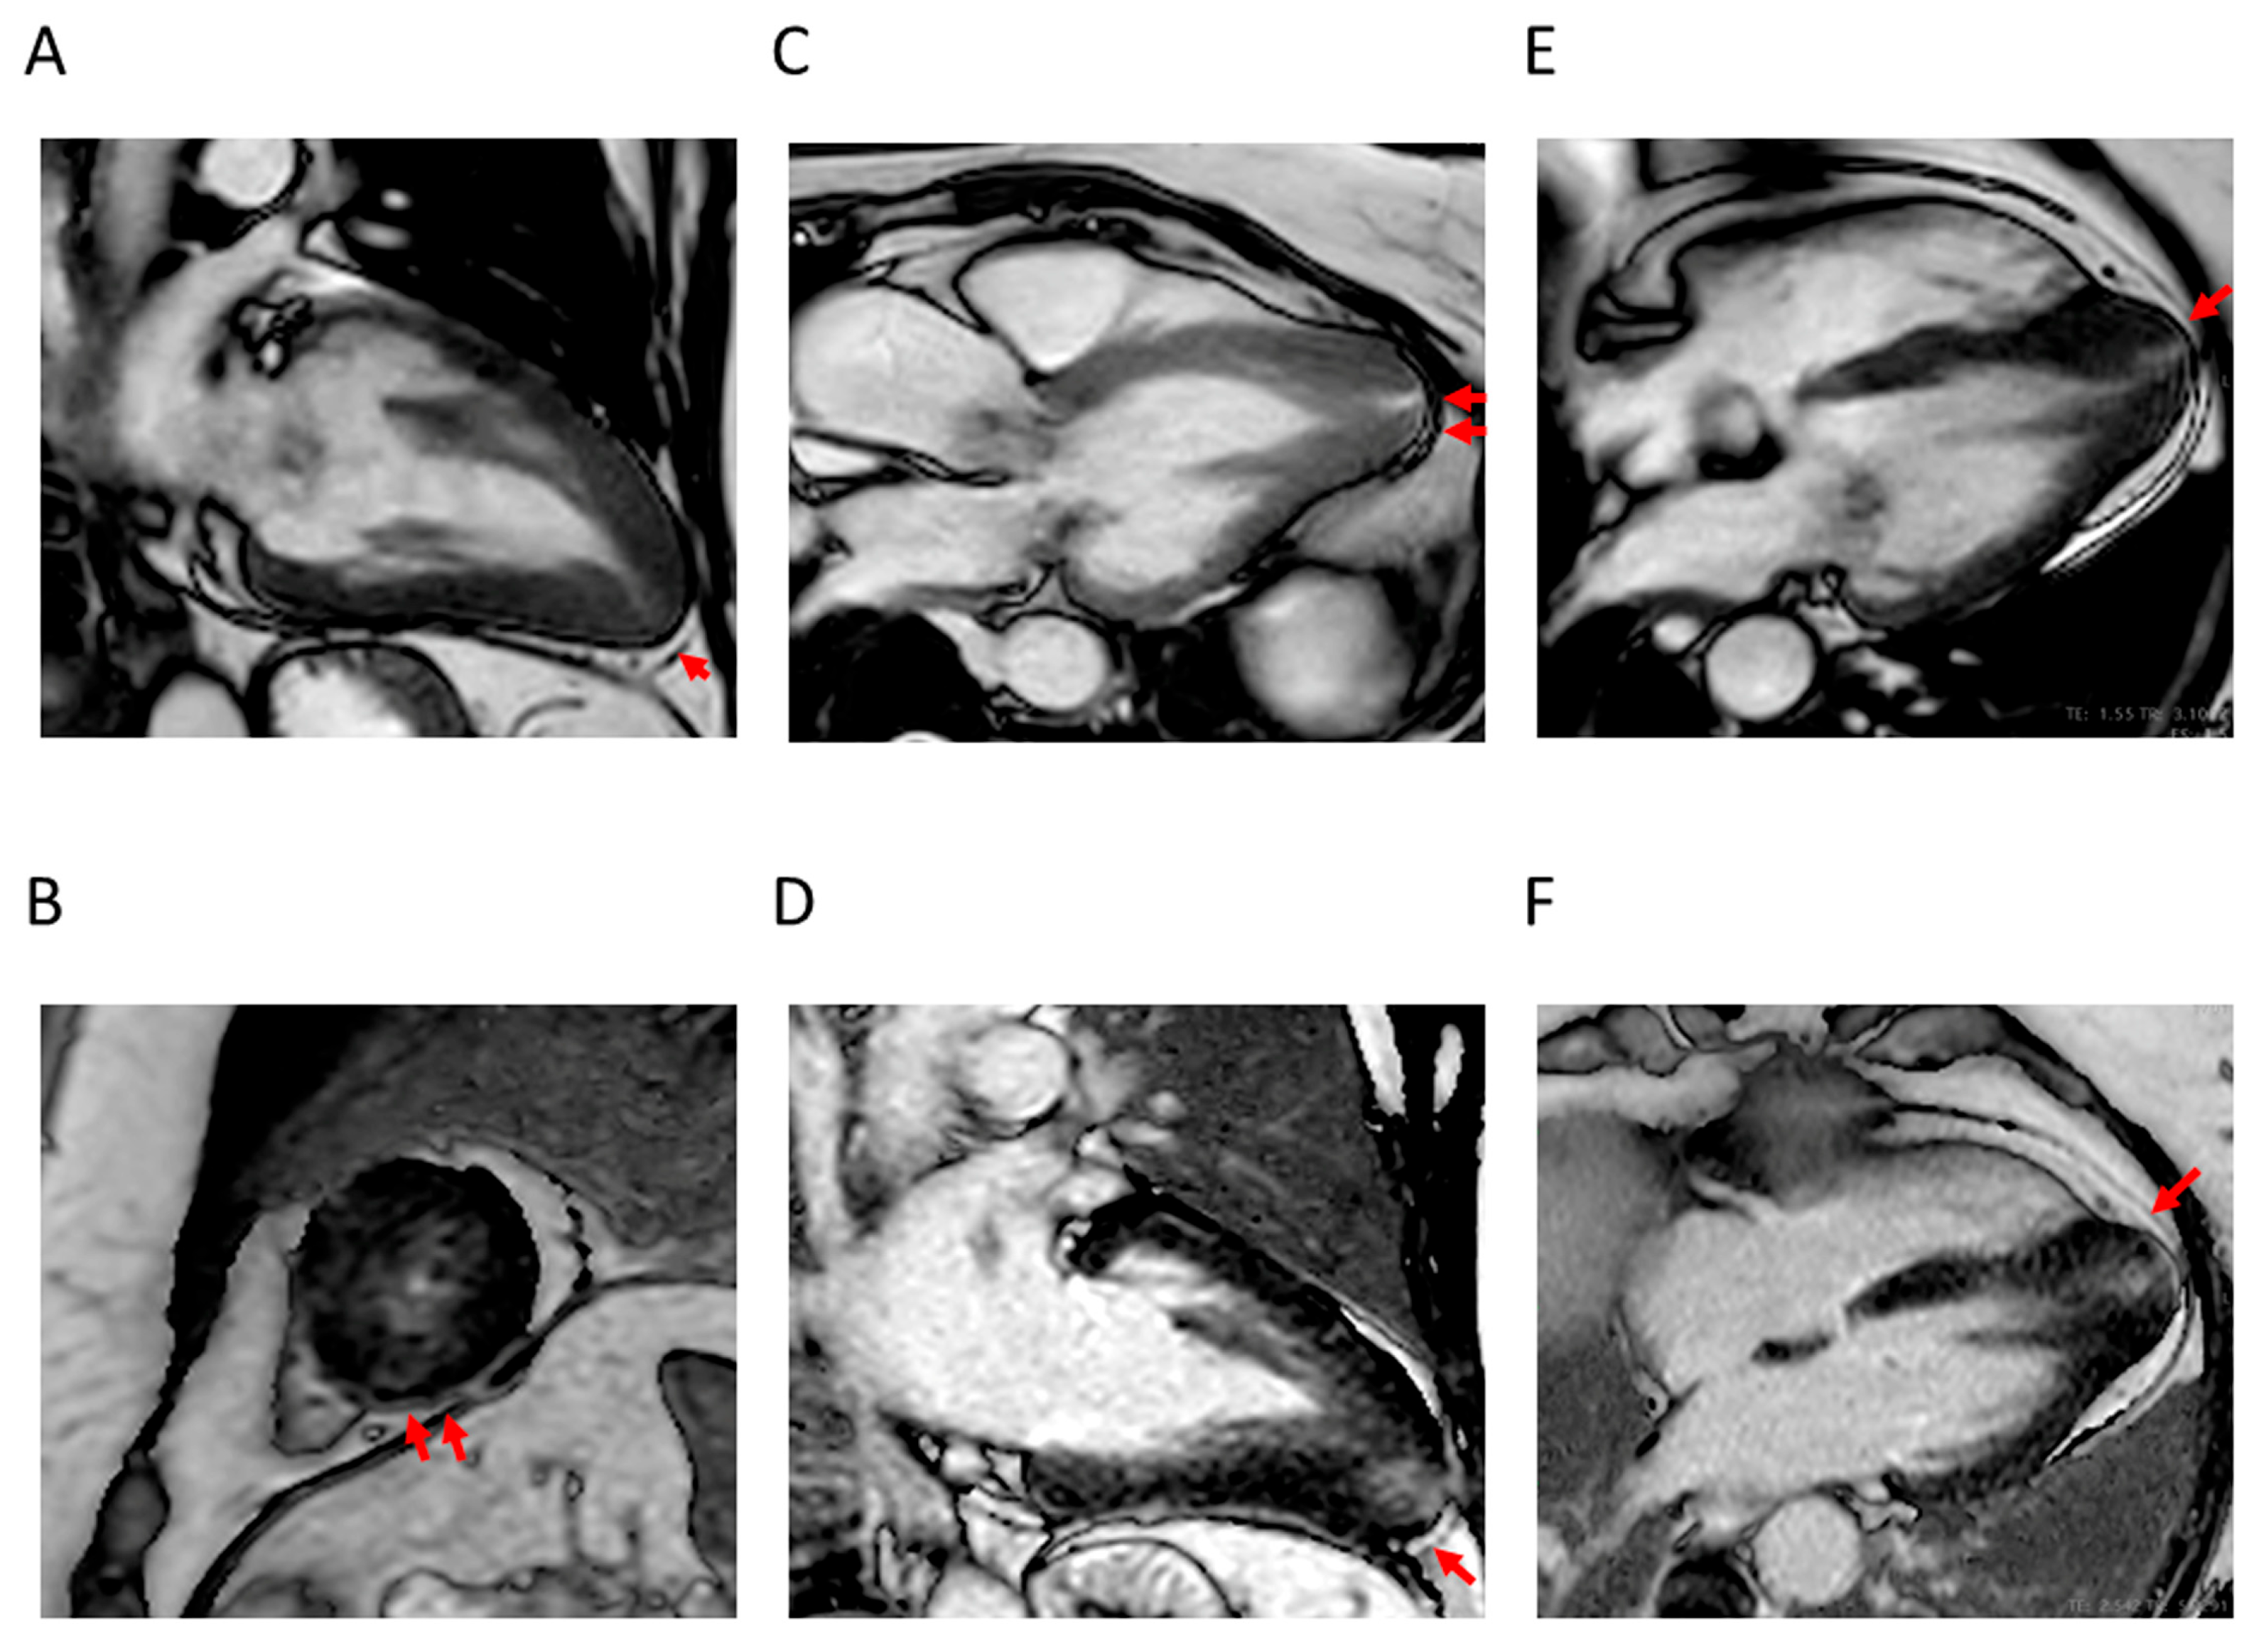

4.1. LV Hypertrophy

4.2. Apical Aneurysm

4.3. LVOTO

4.4. LV Function